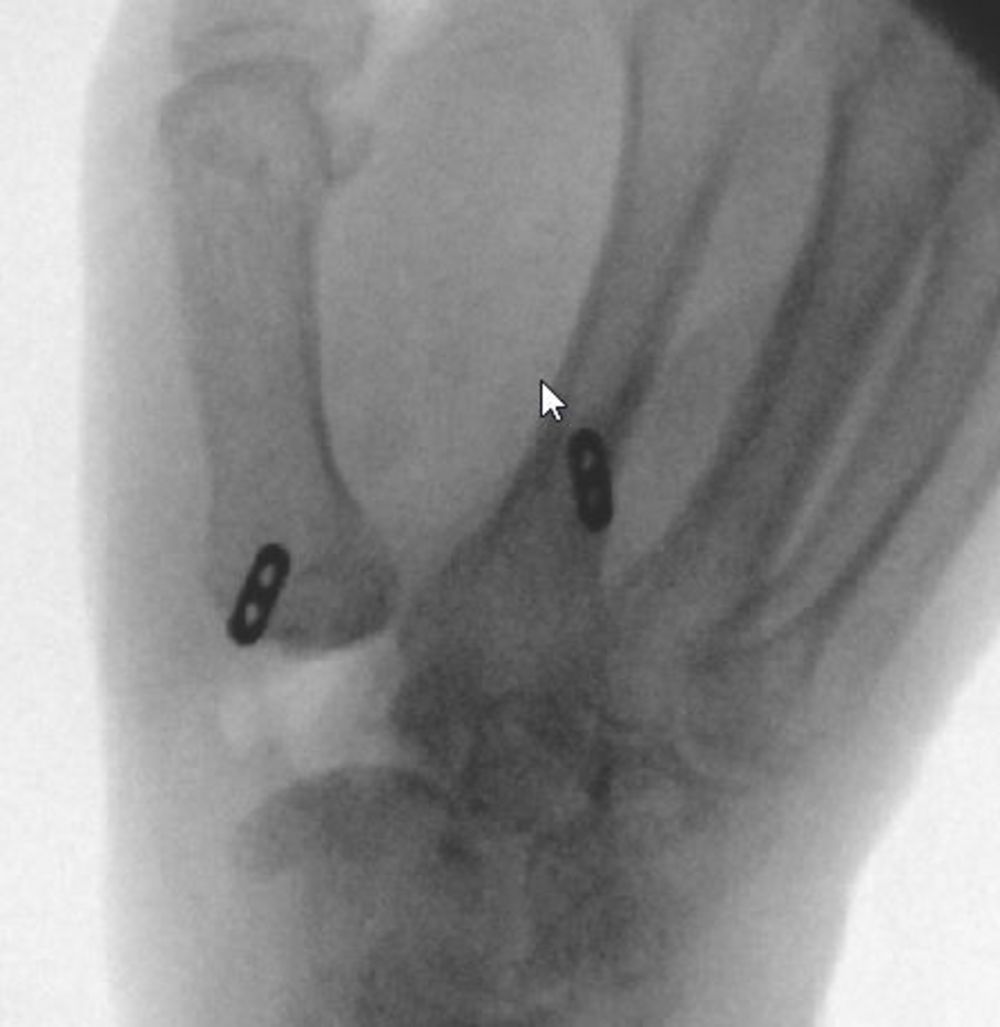

Ist die Linderung nicht hinreichend oder nach einer Weile wieder aufgebraucht, ist eine vollständige Entfernung des großen Vieleckbeines (Trapezektomie) der Goldstandard. Bei mitbetroffenem STT-Gelenk ist diese Methode primär angezeigt. Teilweise werden hierbei die gelenktragenden Anteile des kleinen Vieleckbeines auch entfernt.

Um ein Absinken des ersten Mittelhandknochens zum Kahnbein zu vermeiden, wird der erste Mittelhandknochen über einen Fadenzügel zur Basis des zweiten Mittelhandknochens aufgehängt.